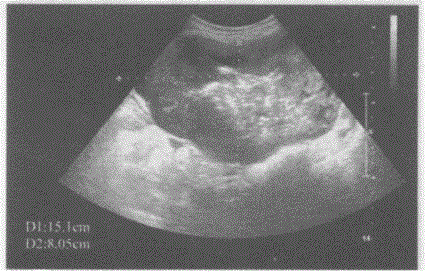

问题 临床资料:女,77岁,自述腹胀、腹痛2月余,加重排便困难、大便变形2周。 临床物理检查:左下腹可扪及一肿物,质硬无活动,轻度压痛。 超声综合描述:左下腹部可见15.0cm×8.0cm×15.0cm假肾样混合性回声区,边界清晰,壁厚1.7cm,中部可见气体样强回声。 超声提示:

选项 A.局限性小肠壁增厚 B.小肠壁增厚肠道实性占位(小肠间质瘤) C.放射性肠炎 D.肠结核

答案 B